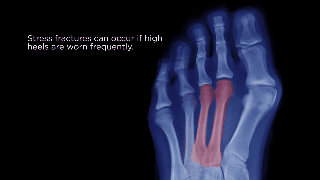

Recent studies are finding a plethora of health problems can stem from your feet being subjected to this amount of pressure for extended periods of time. Women have reported side effects ranging from bunions to stress fractures to to back pain. Find out more about these and other signs you need to watch for that can indicate damage is being done to your feet.

Oftentimes the first sign of the overwearing of high heels is the presence of calluses on the big toe or the outside of the foot near the pinky toe. Severe calluses on toe knuckles can create a hammertoe effect, while calluses on the inside ball of the foot may cause bone malformations known as bunions. Both ailments require medical treatment for reversal and both can recur if high heel wearing persists.

Bunions can be extremely painful. The image below illustrates how they form.